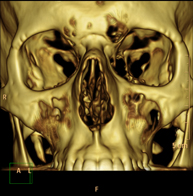

- TC Macizo facial  Prueba radiológica que consiste en obtener imágenes del macizo facial (cara) de alta definición anatómica mediante el empleo de un equipo de TC (Tomografía Computarizada). Indicaciones: tumores, cirugía plástica. Prueba radiológica que consiste en obtener imágenes del macizo facial (cara) de alta definición anatómica mediante el empleo de un equipo de TC (Tomografía Computarizada). Indicaciones: tumores, cirugía plástica.